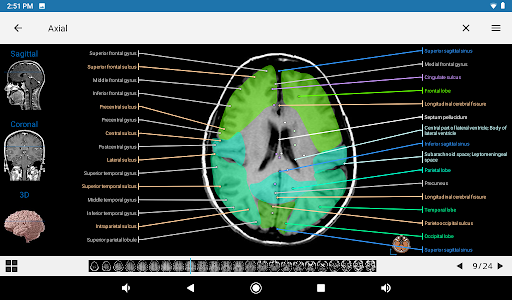

-Two new modules : Brain - TOF and Brain Angiography, Atlas of normal neurovascular anatomy of arteries of the brain on a cerebral angiogaphy.-The interface has been reworked.-A new tab named "QuickLinks" is available, dispatching modules in sections of the human body and allowing you to fast travel to the modules you are looking for.-Fixed small bugs.